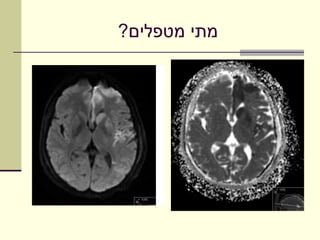

‫מתי מטפלים?‬